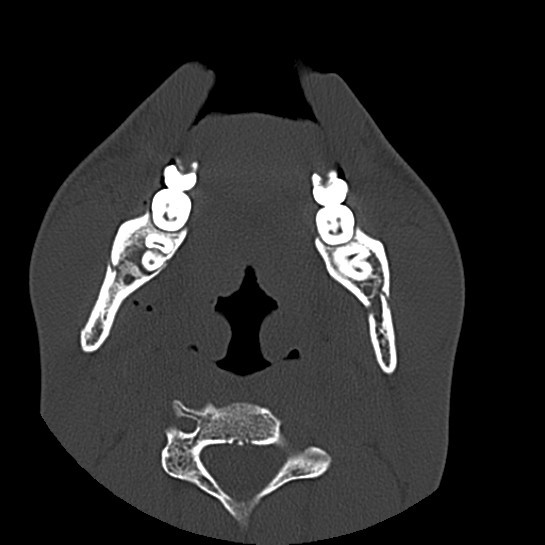

Facial Fracture X-Rays